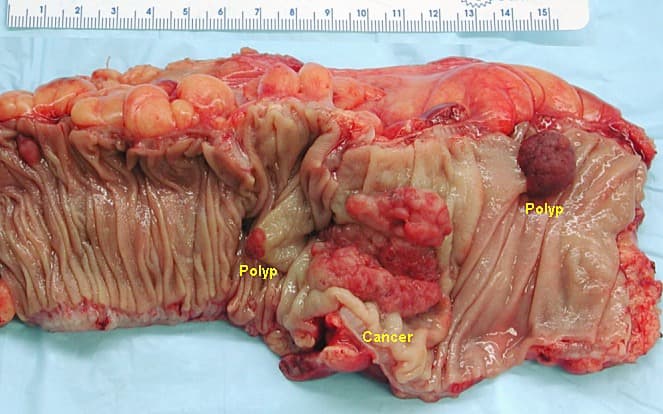

Les polypes adénomateux colorectaux, adénomes colorectaux ou polype adénomateux, s'observent le plus souvent sur le rectosigmoïde avec une fréquence maximale entre 50 et 60 ans. Ils réalisent une formation en saillie sur la muqueuse, arrondie ou polylobée, de 2 à 10 mm de diamètre, sessile ou pédiculée, le pédicule pouvant être très long (5 cm et plus). Il prédispose à l'adénocarcinome colorectal (cancer colorectal). Adénome colorectal sessile (voir polype sessile) Adénome colorectal pédiculé (voir polype pédiculé) En cas de cancérisation, ils doivent être classé en selon la classification de Haggitt des polypes adénomateux cancérisés. L'adénome tubuleux est constitué d'une prolifération de glandes identiques aux glandes de Lieberkühn dont elles naissent. Les cellules sont cylindriques, avec une mucosécrétion sous forme d'une vacuole ouverte au pôle apical. Il peut exister une dédifférenciation marquée par une diminution ou une disparition de la mucosécrétion et un aspect basophile du cytoplasme. Les adénome villeux, plus rares, forment des masses sessiles ou polypoïdes, molles, recouvertes de mucus, et constituées de fines digitations. Elles sont constitués d'axes conjonctifs recouverts d'une couche de cellules épithéliales cylindriques et mucosecrétantes, comportant ou non une mucosécrétion comme l'épithélium colique superficiel dont elles dérivent. Comme les adénomes tubuleux, les tumeurs villeuses peuvent présenter des aspects dédifférenciés. Les récidives après exérèse sont très fréquentes. Les adénome tubulo-villeux sont mixtes, à la fois tubuleux et villeux. L'adénome festonné est également un sous-type de polype festonné. Il est mixte entre un adénome tubuleux/villeux et un adénome festonné est également un sous-type de polype festonné. Dysplasie de bas grade Dysplasie de haut grade Au cours de la progression tumorale, certains adénomes peuvent se transformer (se cancériser) avec apparition dans un adénome siège d'une dysplasie de haut grade, d'un foyer d'adénocarcinome colorectal invasif envahissant la muqueuse (« polype malin »).